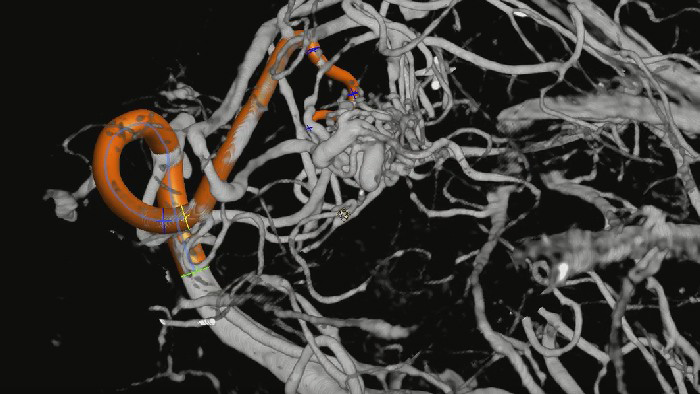

SmartCT Angio provides a volumetric view in a few seconds2 to assist assessment of feeding arteries, draining veins, arterialized veins, nidus and ruptured or unruptured pathology to guide decision making. 3D volumes are visualized with high spatial resolution and automatic patient movement compensation to enhance visibility of critical details.

SmartCT Vaso provides high resolution 3D imaging that reveals key information about cerebral vascular structures to support the highest possible spatial assessment of vessels in the soft tissue context.